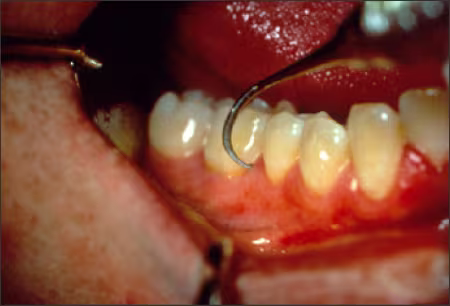

The other end is a sickle type scaler and is good for use on the lingual surface. The thin tip adapts easily and is strong enough to tackle interproximal deposits and line angle stain (Figures 51‑55).

Figure 55. Nevi 1 Scaler - Sickle End.